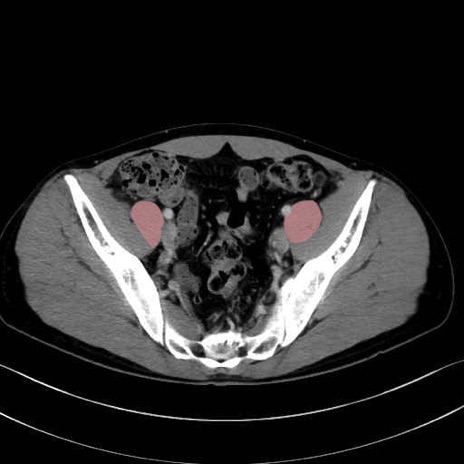

2. 腸腰筋群と骨盤底筋

大腰筋 (Psoas major)

腸骨筋 (Iliacus)